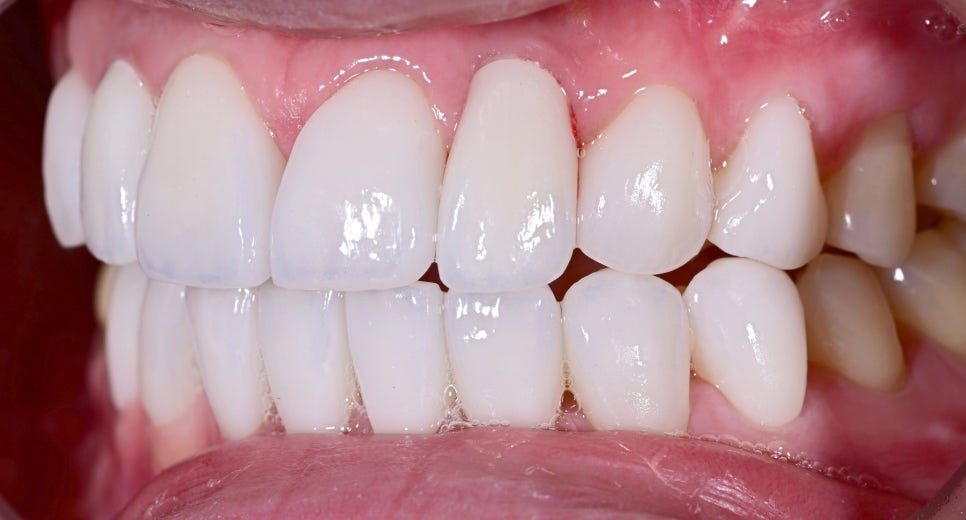

치료 후 변화

치료 후 가장 큰 변화는 “더 이상 임플란트가 따로 놀지 않는다”는 점이었습니다.

기존에는 임플란트 부위가 주변 치아와 미묘하게 다르게 보여 앞니 전체의 통일감을 해치고 있었지만, 치료 후에는 앞니의 색감과 형태, 비율이 훨씬 부드럽게 연결되면서 전체 인상이 한층 정돈되고 자연스러워졌습니다.

또한 너무 차갑거나 인위적인 흰색이 아니라 환자분 이미지에 어울리는 깨끗하고 고급스러운 화이트 톤으로 완성되어 웃을 때의 분위기 자체가 훨씬 밝아졌습니다.

이번 환자분도 오브제로 라미네이트와 임플란트 보철 치료를 통해 기존 임플란트의 부자연스러운 느낌을 개선하고, 자연스럽고 아름다운 미소를 되찾으셨습니다.